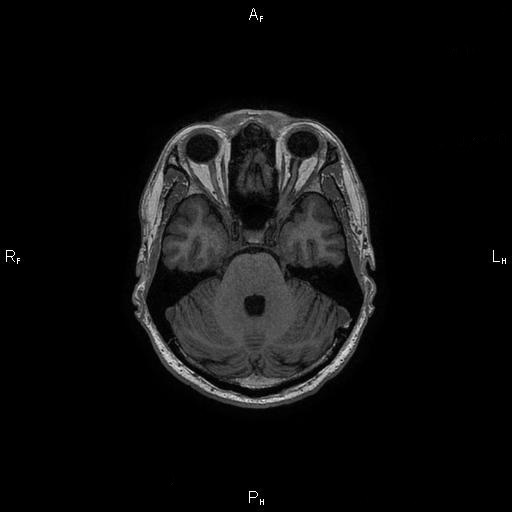

8. Рис. 3а

Тема

Тип Материалы исследования

Посмотреть (11KB)

Метаданные ▾

9. Рис. 3б

10. Рис. 3в

Посмотреть (13KB)